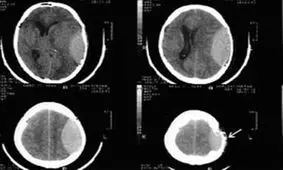

مطالعه جدید نشان میدهد سی تی اسکن که عمدتا در تصویربرداریهای پزشکی استفاده میشود ریسک تومورهای مغزی را افزایش میده…

نخستین آزمایش خون برای تشخیص ضربه مغزی در افراد تایید شد.